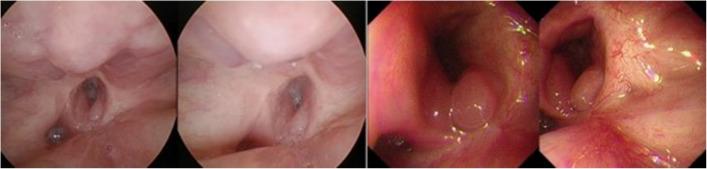

Results: All of the patients demonstrated healing without events, except for one patient who experienced a pharyngocutaneous fistula, which also healed after approximately 2 weeks of dressing changes. With a follow-up of 3-5 years, the median duration of follow-up was 49 months (range = 36-60 months). Eight patients died during follow-up. Moreover, three patients had metastases in the neck, 1 patient had metastases in the lung, and 1 patient discontinued further treatment because of thoracic oesophageal carcinoma with hepatic metastasis. The 5-year overall survival was 42.9%. Among the 14 included patients, two patients developed pharyngoesophageal stenosis, and the remaining patients recovered well. Two patients with pharyngoesophageal stenosis causing feeding difficulties received nasogastric tube nasal feeding and urinary catheter dilation after the scar tissue was removed via coblator plasma surgery at the stenosis and were fed via nasogastric tube for 1-3 months.

Conclusion: As an effective repair method, laryngotracheal flaps have broad application prospects in the repair of the cervical oesophagus after the resection of hypopharyngeal carcinoma with cervical oesophageal involvement. Coblator plasma surgery and catheter dilation may effectively address the problem of eating difficulties in patients with postoperative pharyngoesophageal stenosis.